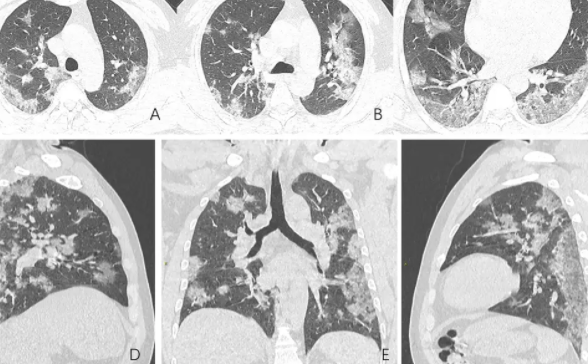

有5个人,肺部已经出现阴影、肺气肿、胸膜粘连等明显肺炎表现,